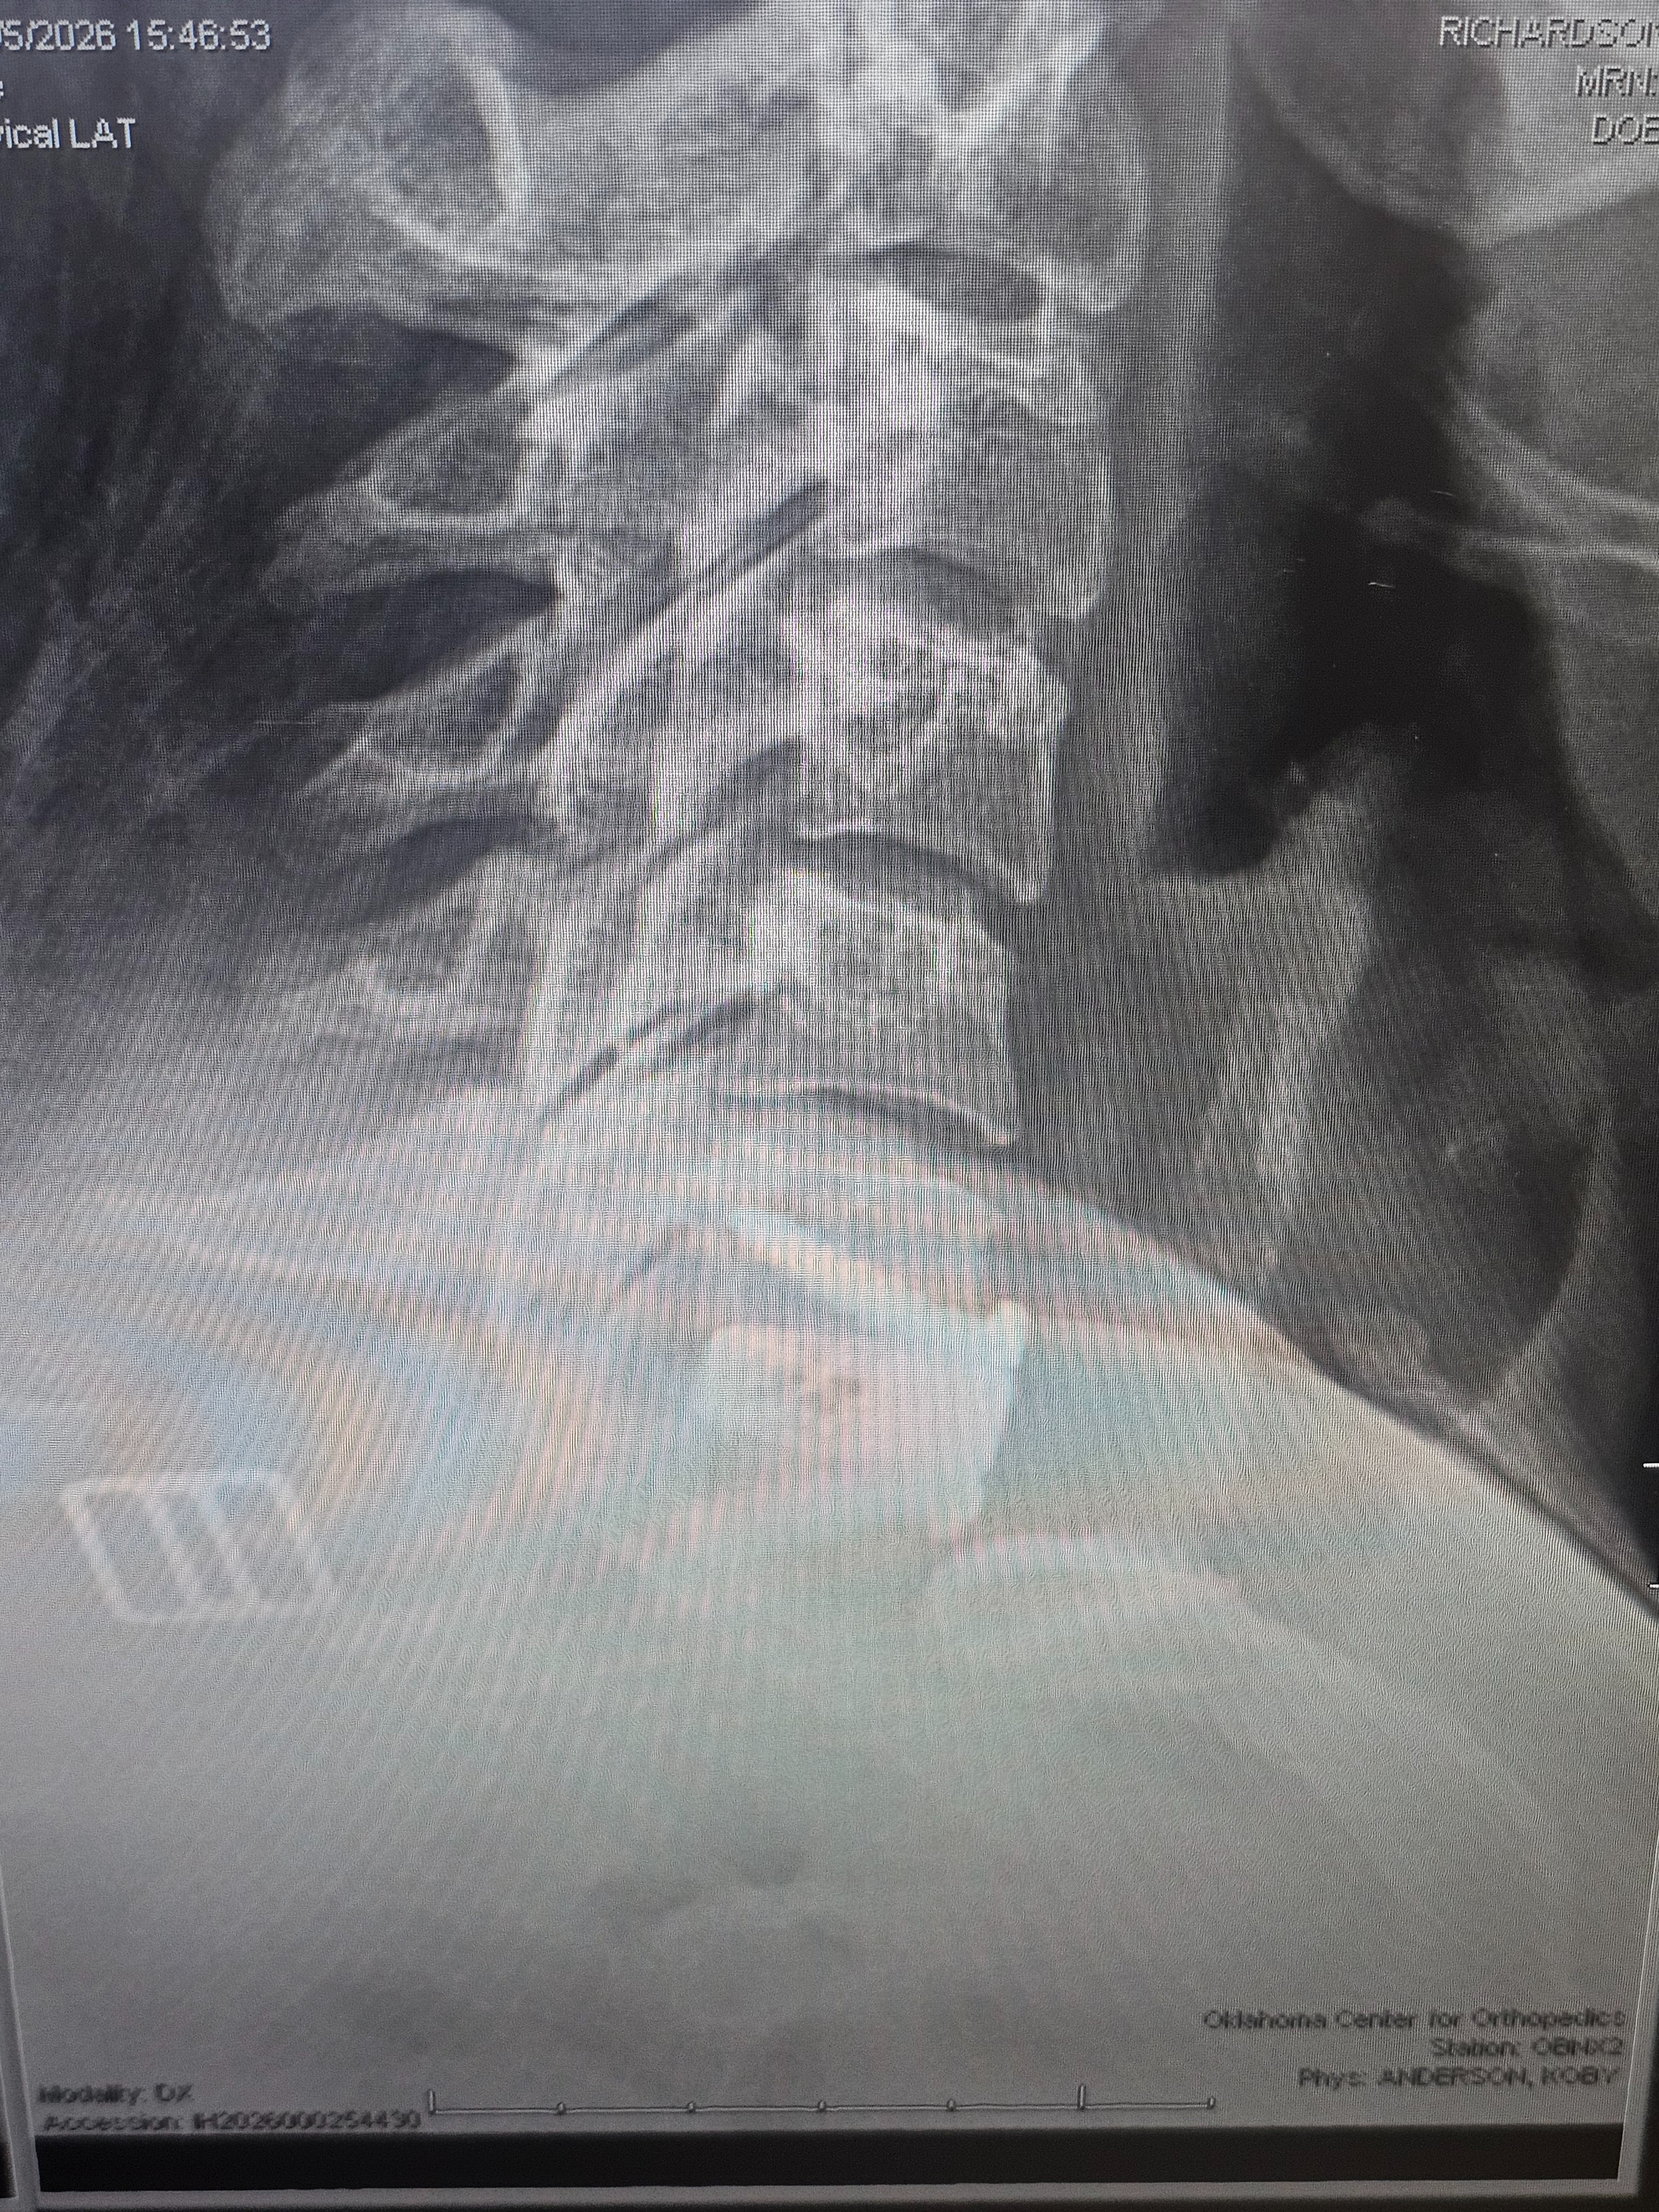

For those who may not know: In 2023 I was in a car accident that caused my disc between c6 and c7 yo herniate 5mm, pinching a nerve. I finally was able to get surgery to fix this in January of this year, but I've been out of work longer than expected and ran out of PTO. Unfortunately I don't exactly have parental support to cushion me in this time (RIP) my community has been saving me through this ❤️